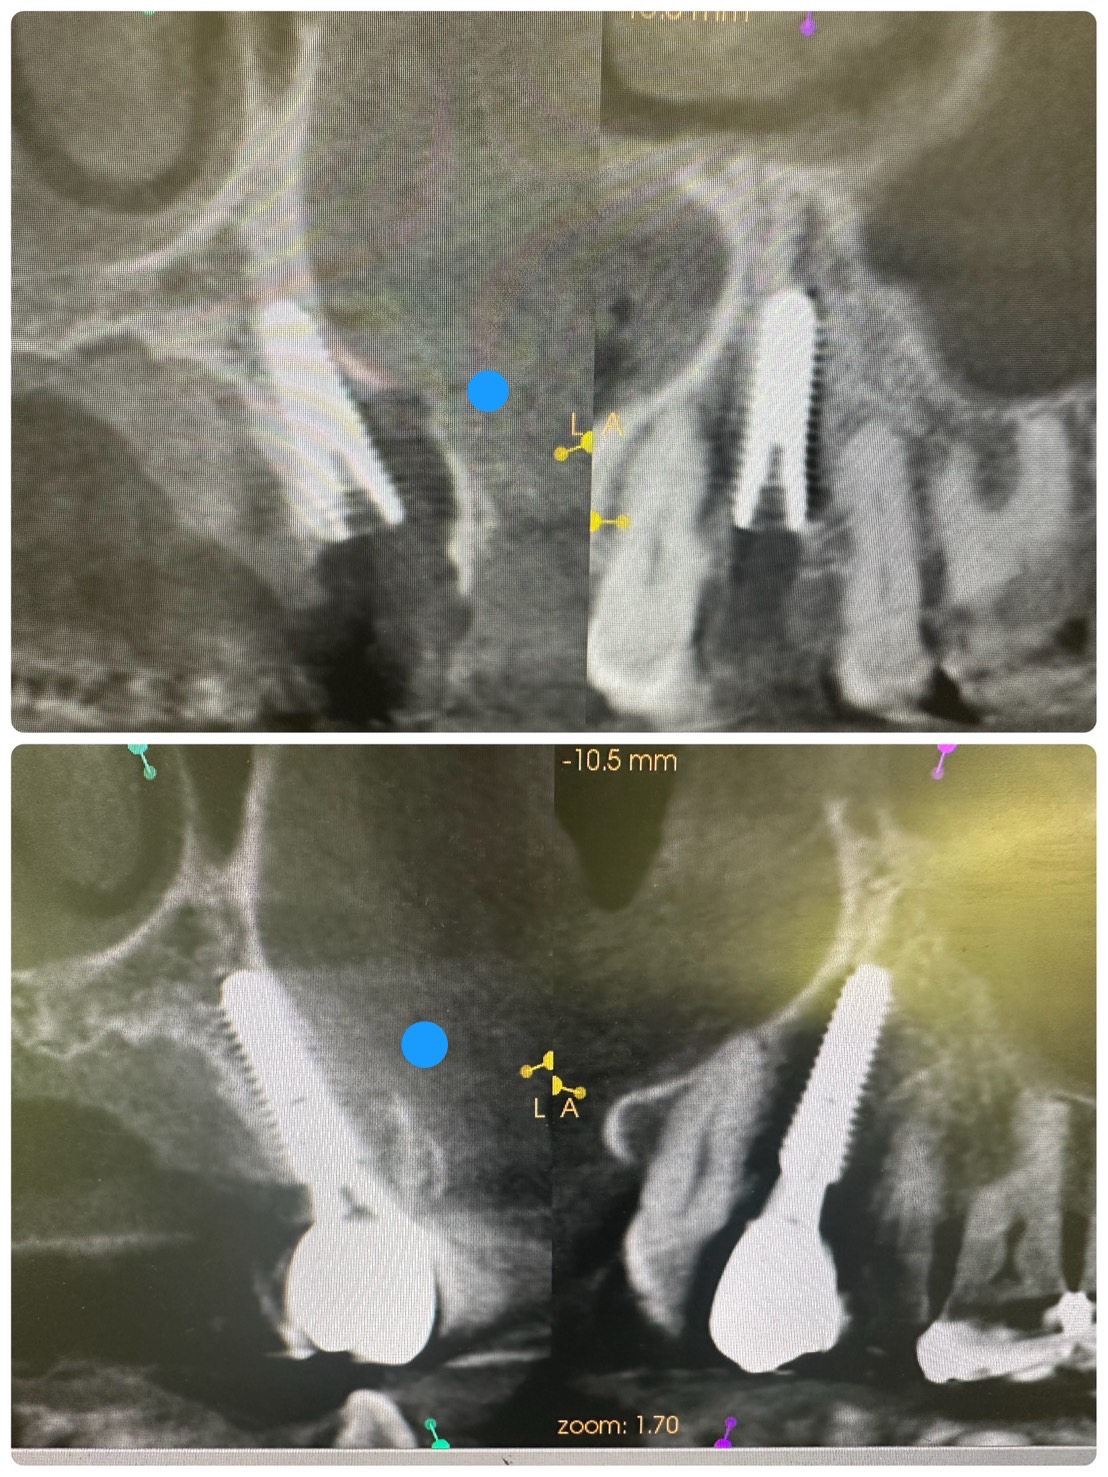

次のお方は、本年4月に抜歯即時、ソケットシールド

セミルーナフラップした方の頬側の骨再生画像確認

ソケットシールドしてるから、吸収なくボリーュミー